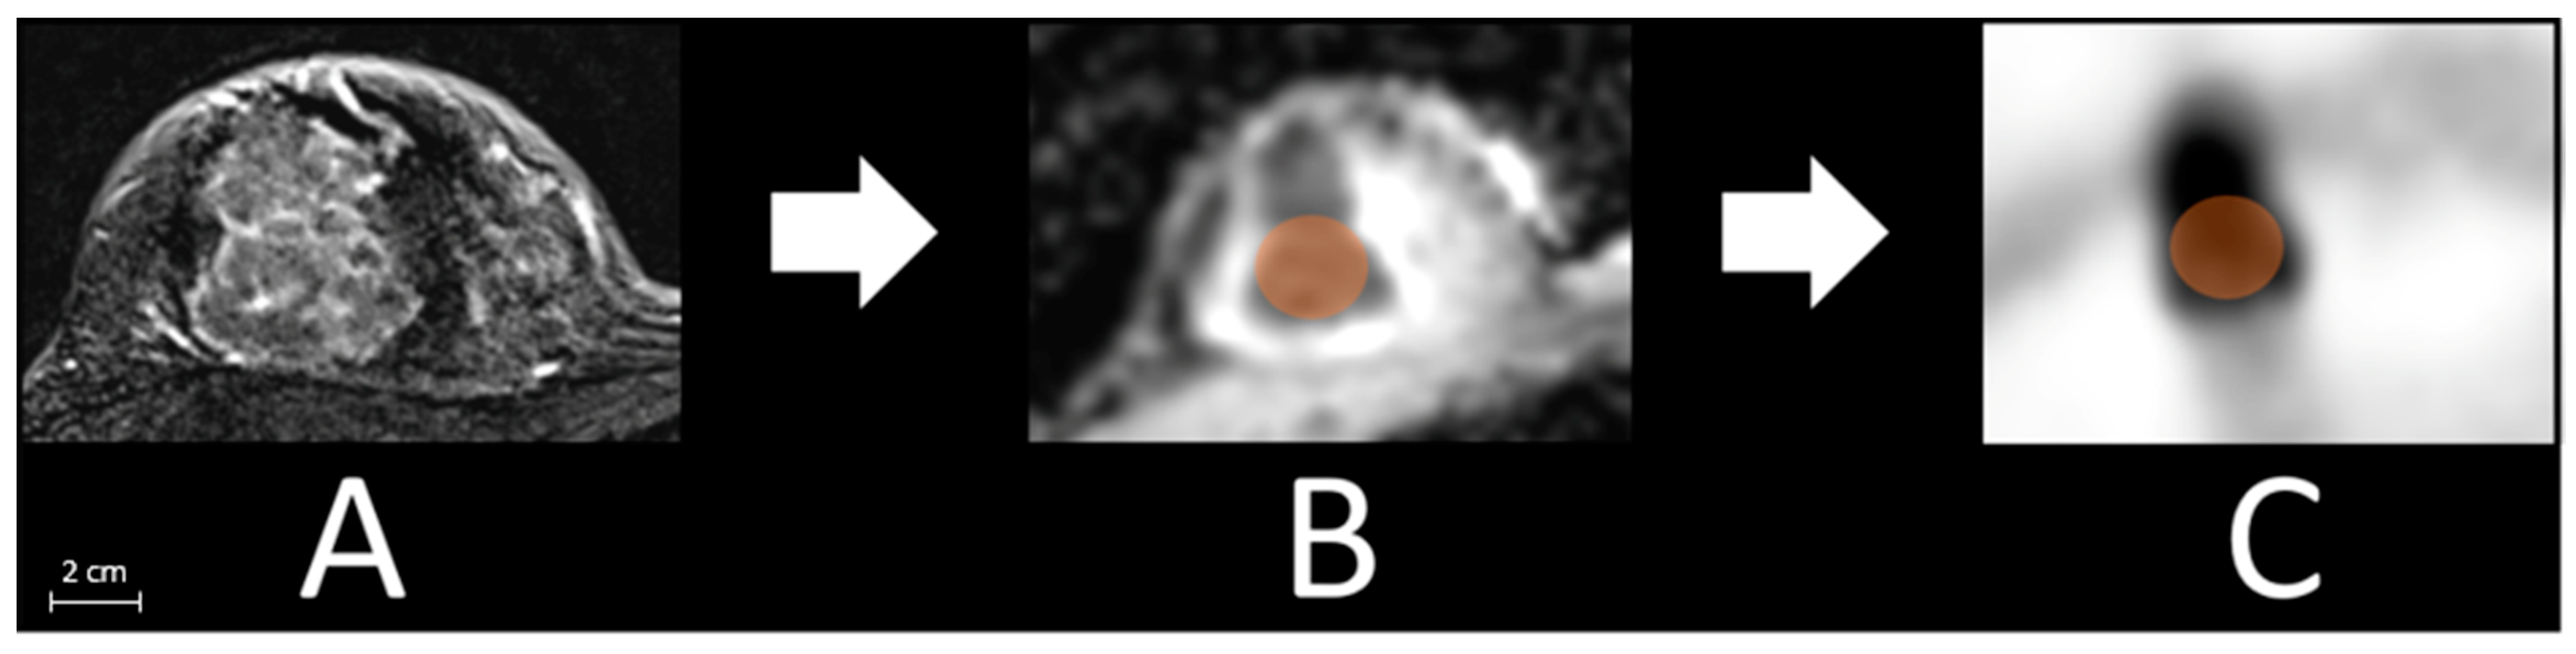

2.3. Image Analysis